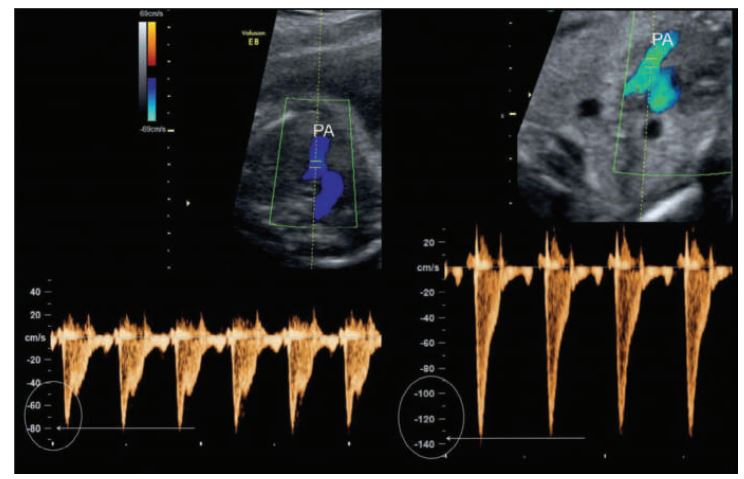

Pulmonic flow patterns are obtained parallel to flow in the high short-axis plane with the Doppler cursor at the level of the pulmonic cusps. The cursor is moved into the main pulmonary artery to map any changes in the flow pattern.

The mean velocity in the pulmonary artery ranges from 60 to 80cm/sec. Note the high-velocity pulmonic flow on the right which could be from. ________PA, Pulmonary artery.

pulmonary stenosis